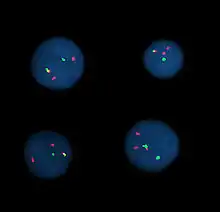

Fluorescence in situ hybridization

Interphase cells positive for a t(9;22) rearrangement

Fluorescence in situ hybridization (FISH) refers to using fluorescently labeled probe to hybridize to cytogenetic cell preparations.

Analysis of FISH specimens is done by fluorescence microscopy by a clinical laboratory specialist in cytogenetics. For oncology, generally, a large number of interphase cells are scored in order to rule out low-level residual disease, generally between 200 and 1,000 cells are counted and scored. For congenital problems usually 20 metaphase cells are scored.